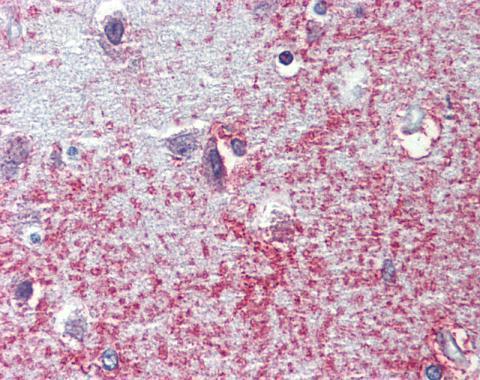

Immunohistochemical analysis of paraffin-embedded human brain, cortex, using APXL(GTX100055) antibody(10 μg/ml).

Antigen Retrieval: Trilogy™ (EDTA based, pH 8.0) buffer, 15min